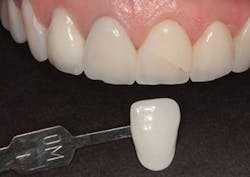

In Figure 1, you can see a close-up view of her smile as it was when she presented. She recently had noticed a fracture in both central incisor crowns and, since replacement was necessary, wanted to investigate the possibilities for improvement. The retracted facial view can be seen in Figure 2. Clinical and radiographic examination showed me that her overall dental health was good, with no periodontal disease or active caries. The patient expressed an interest in widening her smile and achieving a lighter color. The shade she desired was OM1 on the Vita Toothguide 3D-Master shade guide (figure 3).

Figure 3: The patient’s desired shade compared to her initial smile